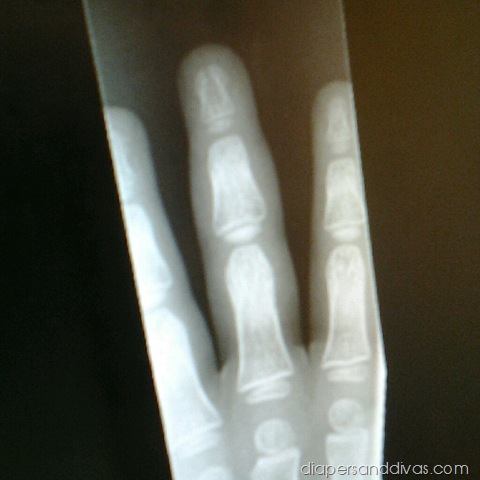

See that split down the middle of the top bone in his middle finger? Yep. Broken.